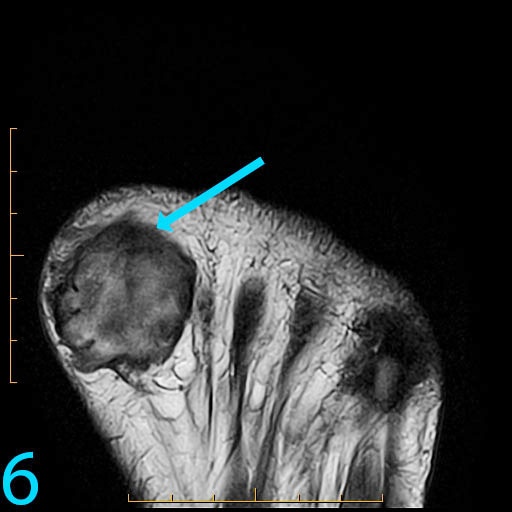

This 18-year-old female presents with a palpable soft tissue mass subjacent to the first metatarsophalangeal (MP) joint that she has noticed for 1-2 months. It is painful with shoes and ambulation, and you are evaluating her for a soft tissue tumor. What is the cause of her problem, and what pertinent negatives must you notice?

This patient has a so-called "pressure lesion" due to ambulation, with associated adventitial bursa/pseudobursa formation within. It is a chronic process. This is manifested as a large, ovoid mass-like structure within the subcutaneous soft tissues along the plantar aspect of the first MP joint and sesamoid bones (arrow). It is well-circumscribed and demonstrates a mildly lobulated configuration. There is peripheral signal hypointensity indicating a rim or rind of fibrosis, and there is intermediate to high T2 signal centrally, suggesting a component of complex fluid. The major differential diagnosis is fibroma of tendon sheath. This is a counterintuitive diagnosis as fibrous lesions are typically dark on all pulsing sequences. But, fluid signal from the tendon sheath may be found in this specific fibrous tumor. So, fibromas of tendon sheath are typically hyperintense centrally.

While the lobulation of the lesion medially is reminiscent of plantar fibromatosis, the constellation of findings remains most compatible with a giant pressure lesion. Fibromatosis (non-aggressive type) occurs more proximally in the middle aponeurotic cord of the plantar fascia. The findings are not suspicious of an aggressive neoplastic lesion (based on location and concentric shape), and you can also rule out MP joint capsulitis and Morton's neuroma because of location. You should always rule out plantar plate tear along the second MP joint on thin section sagittals if you have a large pressure lesion under the second metatarsal head. For more case review, visit MRI Online.